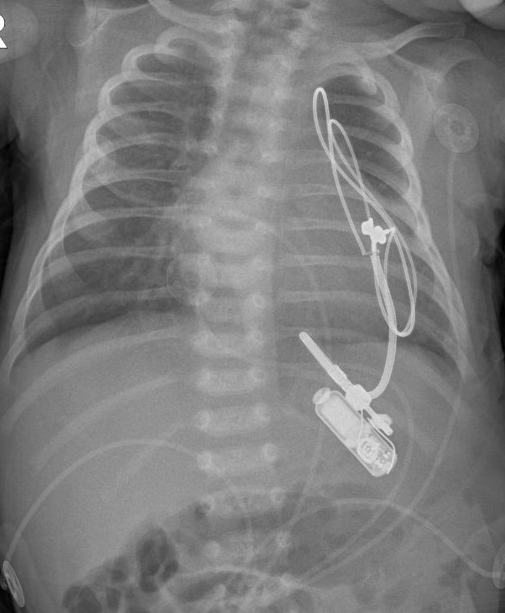

mikey-oliveri-pacemaker-credit-hassenfeld-childrens-hospital-at-nyu-langone.png

An X-ray image of the pacemaker.

NYU Langone / Hassenfeld Children’s Hospital

Tan and other members of the pediatric heart team filed for emergency approval to use an adapted version of the device that was suitable for babies. It’s the smallest pacemaker in the world. Only about 50 such devices have ever been implanted in the United States. Kumar said the adapted version is inserted and placed over the heart with just one small surgical incision during a 75-minute procedure.